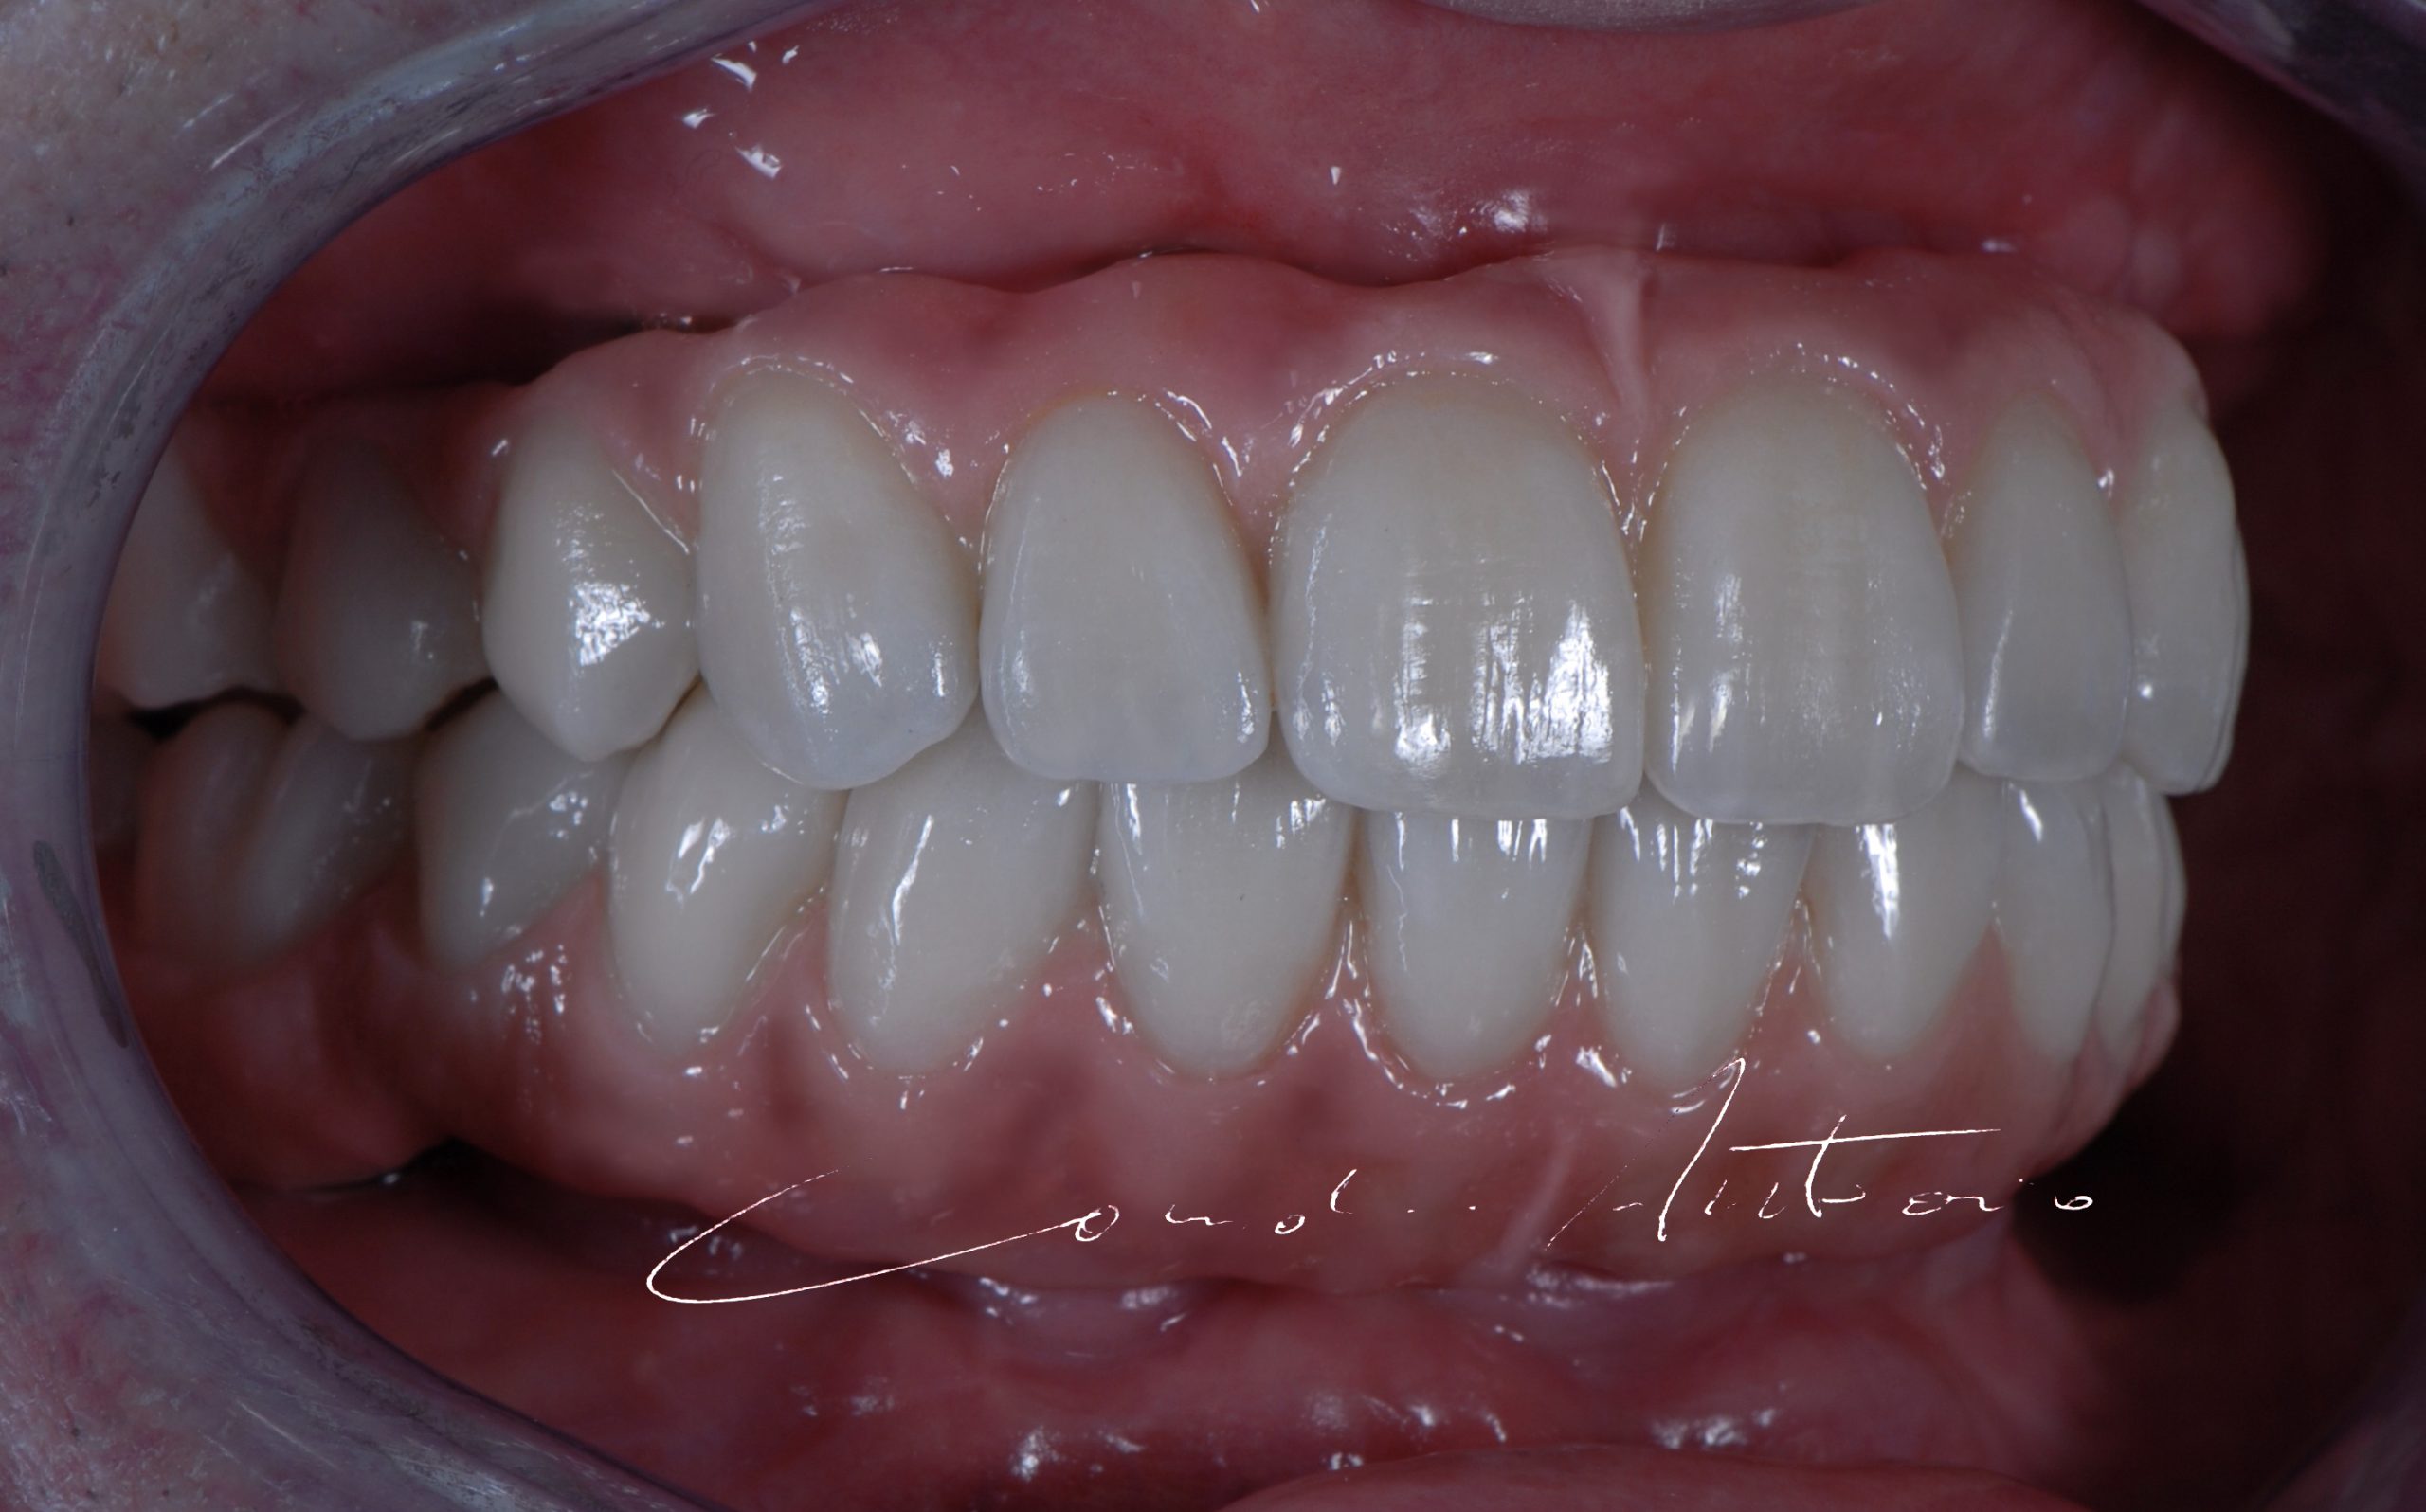

Zirconia Full Arches

Complete restorations from traditional impressions and digital files using different processing procedures and materials.

Implants & Crowns

Prosthetics from traditional impressions and digital files on preparations and implants.